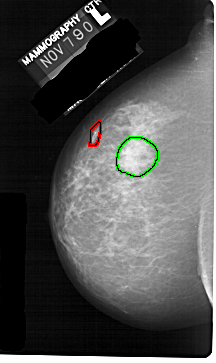

FILE: A_1251_1.LEFT_CC.OVERLAY

TOTAL_ABNORMALITIES 1

ABNORMALITY 1

LESION_TYPE CALCIFICATION TYPE PLEOMORPHIC DISTRIBUTION LINEAR

ASSESSMENT 5

SUBTLETY 5

PATHOLOGY MALIGNANT

TOTAL_OUTLINES 1

BOUNDARY

ABNORMALITY 2

LESION_TYPE MASS SHAPE IRREGULAR MARGINS ILL_DEFINED

ASSESSMENT 4

SUBTLETY 3